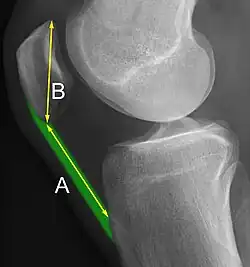

A patella baja is a low-riding patella. A long-standing patella baja may result in extensor dysfunction.[6]

The Insall-Salvati ratio helps to indicate patella baja on lateral X-rays, and is calculated as the patellar tendon length divided by the patellar bone length. An Insall-Salvati ratio of < 0.8 indicates patella baja.[7]

- ^ a b Douglas Dennis (2017-02-25). "TKA in Patella Baja (Infera)". Orthobullets. Retrieved 2019-02-08.